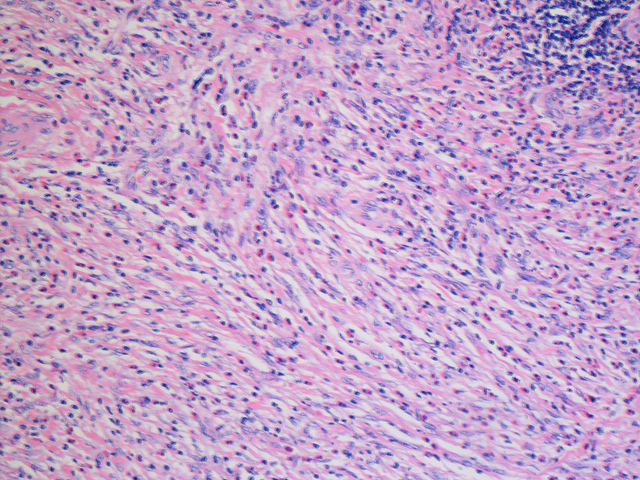

I f you want to learn how to treat fibroids, it is important you first appreciate that there is no single best approach to treating this disease. You should talk with a qualified physician about options for symptom relieve if you have any symptoms. For women with the disease experience no signs or symptoms, watchful waiting can be the better choice. Since fibroids rarely interrupt the pregnancy, are not cancerous, and tend to shrink after menopause, such women do not have to go for treatment unless advised otherwise by a qualified medical doctor. Professional guidelines on how to treat fibroids provide that medications target hormones that regulate the menstrual cycle of the patient. The objectives of any fibroids treatment method are not to eliminate but shrink the fibroids. Here are the treatment methods. GN-RH Agonists GN-RH agonists stop estrogen and progesterone production. By doing so, the medication puts the patient into a temporary postmenopausal state. Consequently, that makes the end of menstruation and fibroids shrink. Doctors recommend that people should use GN-RH agonists for over three to six months since symptoms return when the medicine is stopped, and long-term use also increases the risk of losing bones. Progestin-Releasing Intrauterine Device Another medical way of treating fibroids is using the progestin-releasing intrauterine device. This device can relieve heavy bleeding. It only provides symptom relief but does not either make them disappear or shrink. Other Medications There are also other medications that a doctor can recommend to a patient. Oral contraceptives are an excellent medical way of treating fibroids. Non-hormonal medications such as Nonsteroidal anti-inflammatory drugs are also effective in relieving pain related to this medical condition. In some cases, doctors recommend that patients take vitamins and iron, especially if they are experiencing heavy menstrual bleeding and anemia. Conclusion Medications option is a common and effective way of treating fibroids, and some of the medication choices are using GN-RH agonists, progestin-releasing intrauterine device, oral contraceptives, Nonsteroidal anti-inflammatory drugs, and taking vitamins and iron. Knowing how to treat fibroids could help a patient understand the best treatment choices and how they work in the body. [Photo: flickr.com]